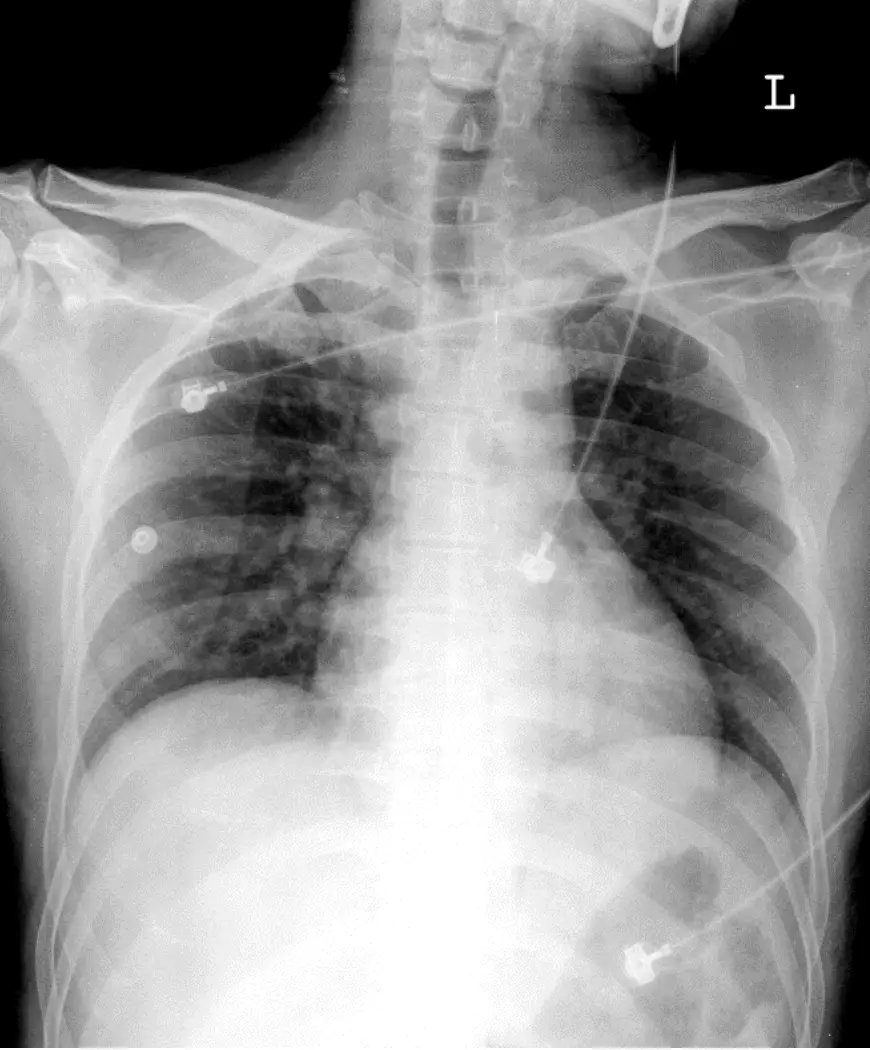

病人36歲男性突然喪失意識有一個小時之久,乃急往醫院求診,時血壓96/56 mmHg 心跳: 105/min,呼 吸: 20/min及體溫: 36.2℃。病人日前牙疼至診所治療,使用ibuprofen, cephalexin 及胃藥,十點入睡,在 深夜裡聽見呼吸喘鳴,4 AM不醒人事並有癲癇發作及尿失禁。理學檢查顯示E1M4V2,半小時後清 醒,有嘔吐及頭痛之表示,未有神經及其他異常所見。CXR 及心電圖如圖,前後相隔二小時。血液生化 有K⁺ 2.8 mEq/L, Na⁺ 141 mEq/L, AST 79 U/L, ALT 98 U/L, Cr 0.97 mg/dL, BUN 13 mg/dL, Sugar 132 mg/dL, Troponin I 0.04 ng/mL。(附心電圖、胸部X光)。從病人的年齡、性別、病史、發作時間、心電圖 所見、生化檢驗和理學所見,本病例最可能的診斷是:

影像分析:

-

初次就醫心電圖(Arrival ECG)

- V₁–V₃導程明顯見到ST段上抬≥2 mm,呈現先向上凸起後向下傾斜再接負T波的「coved」形態,正是Brugada Type 1型特徵。P波與QRS波群形態無典型RBBB改變,PR間期亦正常,與其他結構性心肌病無關。

- 心率約100 bpm,節律規則,無明顯長QT或delta波。